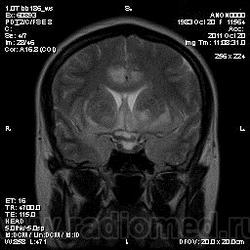

Эта же пациентка... Июль 2011 года....

В анамнезе есть зацепки на энцефалит?Мне ни разу не встречался, поэтому умничать не буду.

А здесь вариант Арнольда-Киари+ платибазия к тому же (?)

мне кажется больше похоже на диффузную глиальную опухоль. Для герпетического нехарактерна локализация и характер контрастирования. Хотя конечно нет правил без исключений..

Евгений Второй, а медиобазальные отделы височных долей - по-моему излюбленная локализация герпетических энцефалитов... Да мне кажется, что серое и белое вещество в равной степени вовлечено в процесс...

Арнольда-Киари можно указать, но вы же понимаете, что он меркнет на фоне основной патологии....

а медиобазальные отделы височных долей - по-моему излюбленная локализация герпетических энцефалитов..

Абсолютно согласен, просто у меня не все картинки раньше загрузились и показалось, что все изменения в лобных долях и базальных ядрах. Снимаю свои возражения.